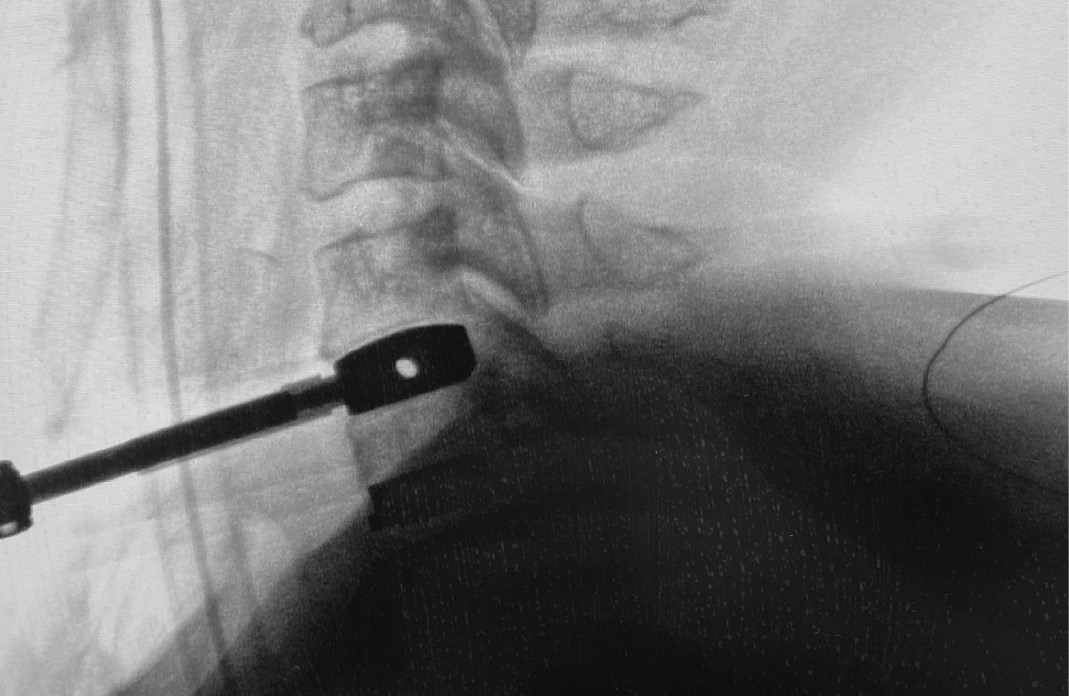

During intra-operative trialing after discectomy and foraminotomies, I felt that the best fit at the C6-7 level was with a prodisc C SK—6mm tall by 18mm deep (Figure 6a). I then performed the discectomy and trialing at the C5-6 level and felt that the prodisc C Vivo was a perfect fit here (Figure 6b).